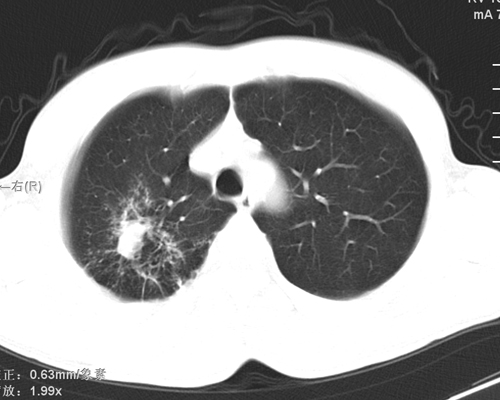

标题: CT24548:男 31 咳嗽 咯血一天 行CT检查 [打印本页]

标题: CT24548:男 31 咳嗽 咯血一天 行CT检查

ct考虑结核 但化验结果示白细胞总数 淋巴均正常,血沉7mm/h不快,请看看结核 支扩还是其他

右肺上叶尖端,后段下叶背段结核伴空洞形成

右肺继发性肺结核伴空洞形成!

右肺继发性肺结核伴右肺下叶背段空洞形成。